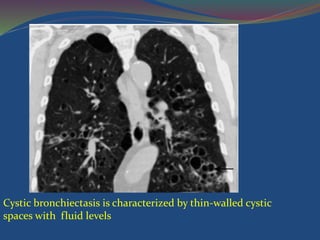

Cystic bronchiectasis

Cystic bronchiectasis is characterized by thin-walled cystic

spaces with fluid levels

Cystic bronchiectasis Cystic bronchiectasisis characterized by thin-walled cystic spaces that connect with proximal airways, with or without

Cystic bronchiectasis ischaracterized by thin-walled cystic spaces with fluid levels